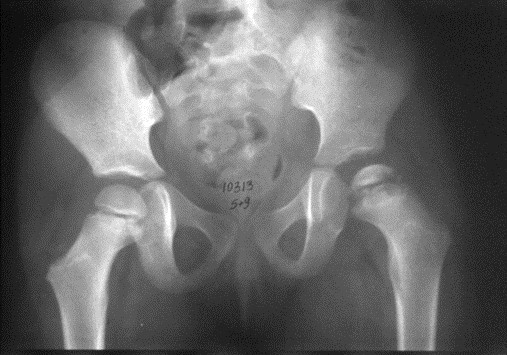

Dziecko w wieku 5 lat i 9 miesięcy zgłosiło się do ortopedy z powodu dolegliwości bólowych lewego stawu kolanowego i okresowych dolegliwości bólowych lewego stawu biodrowego. W badaniu klinicznym stwierdzono niewielkie ograniczenie ruchów odwodzenia w stawie biodrowym i rotacji do wewnątrz. Podczas chodzenia dziecko wyraźnie utyka na kończynę dolną lewą. Objaw Trendelenburga jest dodatni. Wykonany w dniu badania radiogram stawów biodrowych zamieszczony jest poniżej. Obraz kliniczny i radiologiczny przemawia za: